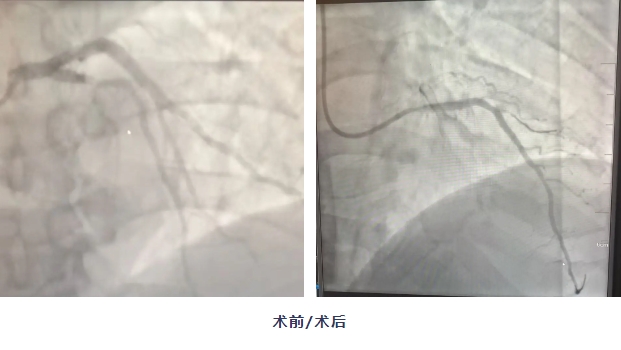

患者長期吸煙,多年高血壓及糖尿病控制不佳,有早發心血管病家族史。BMI(體重指數)29.14,為超重狀態,眼部瞼黃瘤提示脂質代謝異常。經心電圖及相關指標檢查,雖然未達到心梗診斷標準,但主管醫生張偉杰絲毫不敢松懈,他緊盯患者高危背景,在排除神經、骨骼疾病的同時,堅持每2小時動態監測心肌損傷標志物。隨著患者肌鈣蛋白升高,GRACE評分危險等級為極高危,胸痛中心應急流程立即啟動,冠脈造影揭示致命病變——前降支近段95%狹窄。

明確病因后,醫生緊急植入支架,患者癥狀消失,醫護人員懸著的心終于放下了……